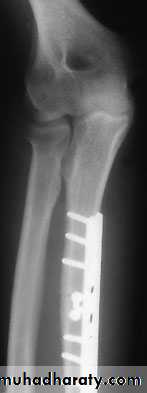

Unless the fragments are in close apposition, reduction is difficult and re-displacement in the cast almost invariable. So open reduction and internal fixation from the outset.The fragments are held by interfragmentary

compression with plates and screws. Bone grafting is advisable if there is comminution.

Adult fracture treatment